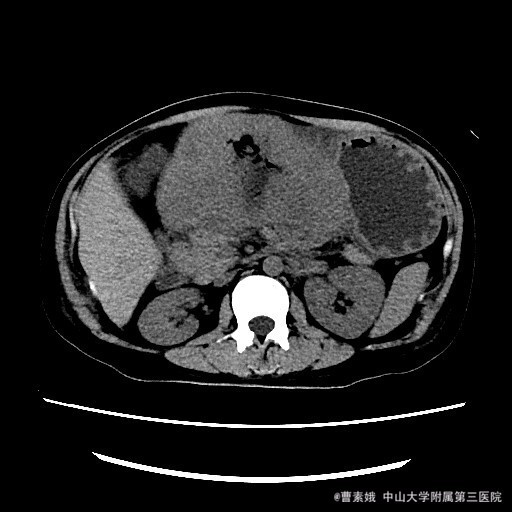

患者:女 37岁 主诉:发现腹部包块伴恶性、呕吐1月余 病史:患者平素一直有胃部不适,偶有胃痛、饱胀感不适,一直口服药物治疗,未见明显好转,1月前自觉腹部包块,并出现恶性、呕吐。呕吐为胃内容物。

查体:左上腹触及一包块,较柔软,余未特殊。 辅助检查:全腹CT平扫+增强示:胃体至胃窦部胃壁弥漫性增厚并软组织肿块,考虑淋巴瘤可能性大。

入院诊断:胃淋巴瘤(?) 治疗:诊断:胃淋巴瘤(?) 治疗:入院后(胃部肿物)送检组织镜下见胃粘膜固有层及肌层结构破坏,并见中等偏大异形淋巴样细胞弥漫浸润,局部成片分布,细胞具有异型性,可见核仁,核分裂象易见,结合免疫组化结果,符合高级别B细胞源性淋巴瘤,考虑滤泡淋巴瘤(FL3b)。组织少,肿瘤成份少,不完全排除弥漫大B细胞性淋巴瘤(生发中心亚型)。建议结合临床。排除手术禁忌症后,于腹腔镜下胃大部分切除术 。 术程顺利,患者恢复较好,建议其进一步化疗,患者表示拒绝后出院。